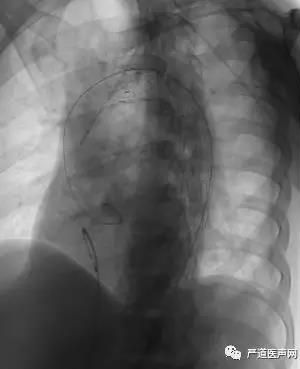

穿刺左桡动脉,置入6F PIG管行主动脉造影可见胸主动脉穿透性溃疡。

经左股动脉沿导丝送入美敦力30*200mm胸主动脉覆膜支架,释放支架成功。